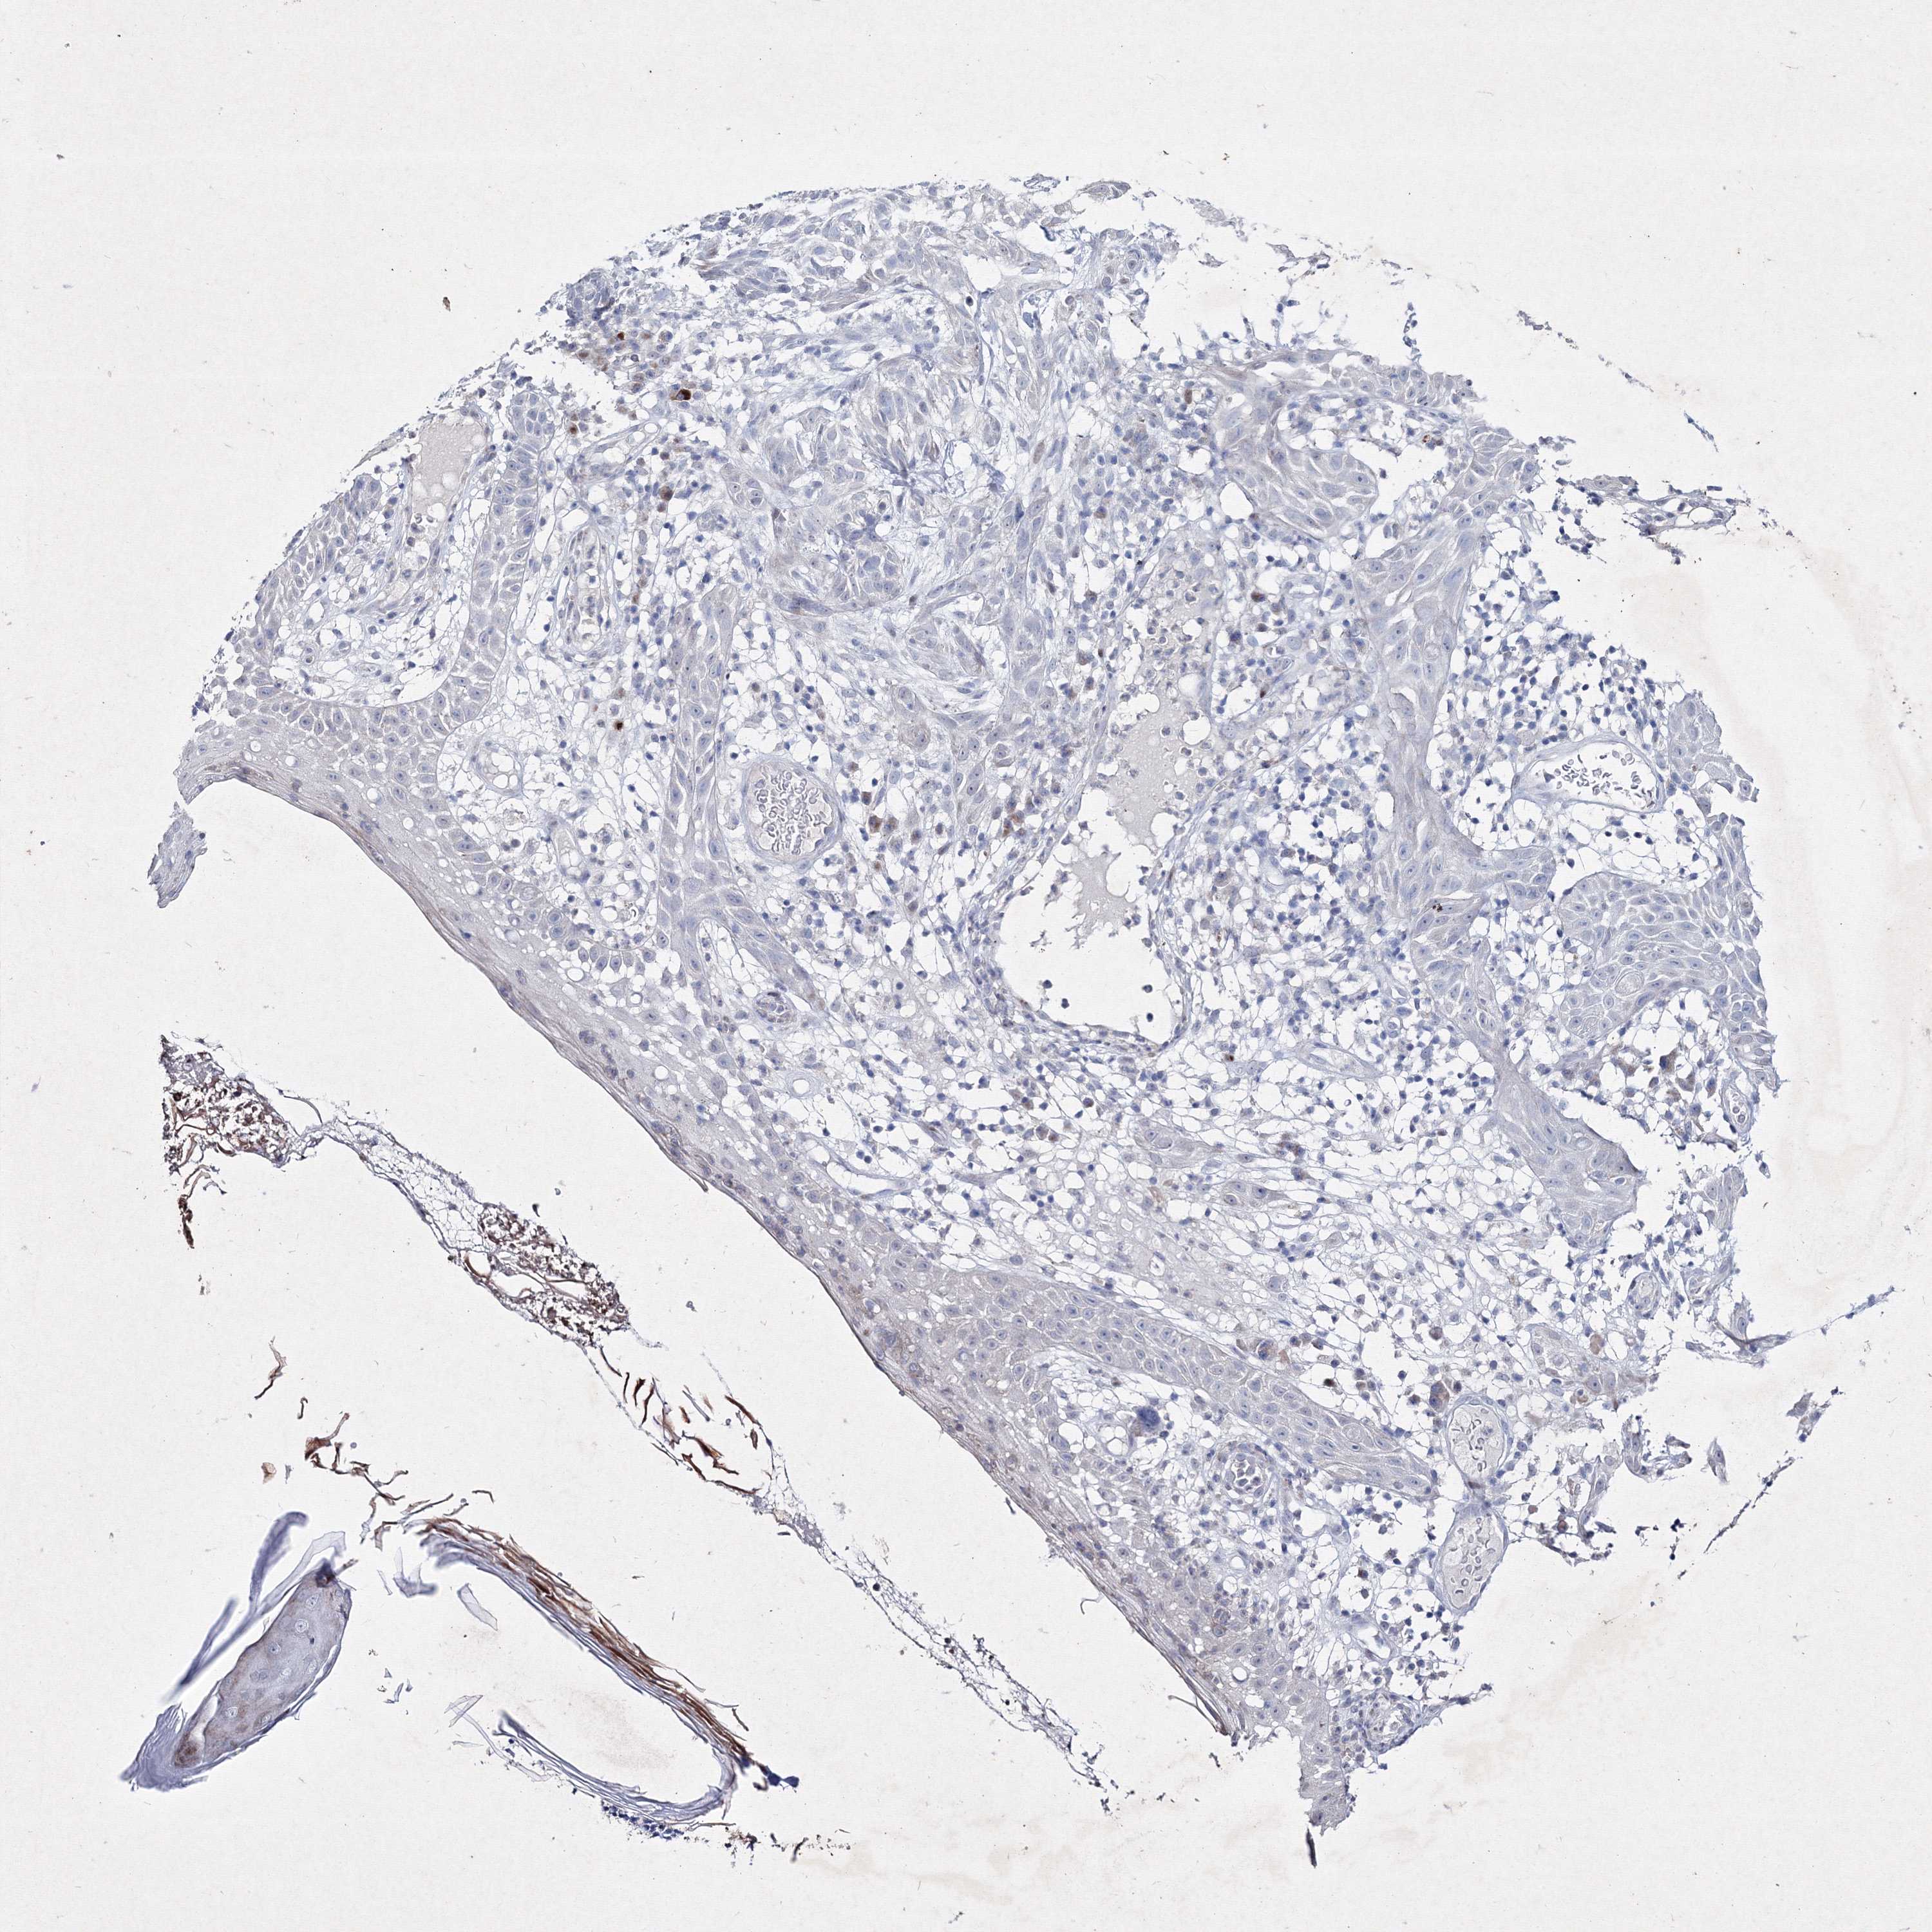

SKIN CANCER - Protein expressioni

A mouse-over function shows sample information and annotation data. Click on an image to view it in a full screen mode. Samples can be filtered based on level of antibody staining by selecting one or several of the following categories: high, medium, low and not detected. The assay and annotation is described here.

Antibody stainingi

Antibody staining in the annotated cell types in the current human tissue is reported as not detected, low, medium, or high, based on conventional immunohistochemistry profiling in selected tissues. This score is based on the combination of the staining intensity and fraction of stained cells.

Each image is clickable and will lead to virtual microscopy that enables deeper exploration of all samples and also displays staining intensity scores, fraction scores and subcellular localization as well as patient and tissue information for each sample.

Antibody HPA037659

Antibody HPA037660

Staining

High

Medium

Low

Not detected

Intensity

Strong

Moderate

Weak

Negative

Quantity

>75%

75%-25%

<25%

None

Location

Nuclear

Cytoplasmic/membranous

Cytoplasmic/membranous,nuclear

Basal cell carcinoma

Squamous cell carcinoma, NOS

Squamous cell carcinoma, metastatic, NOS